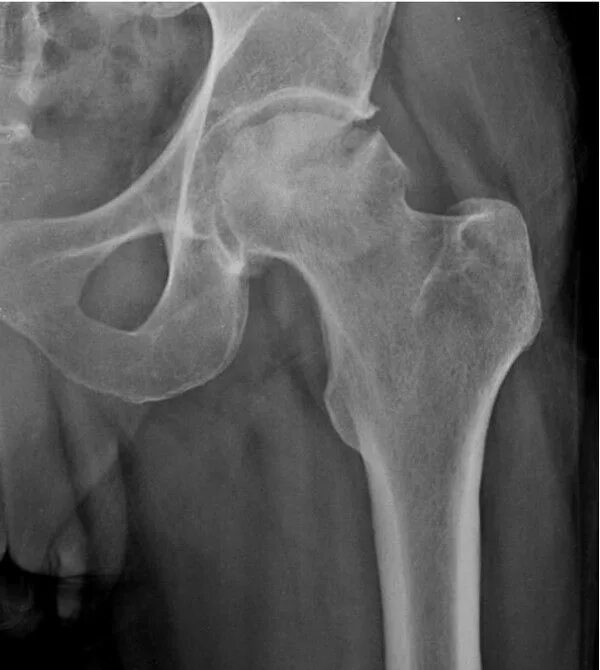

Аваскулярный некроз тазобедренного сустава